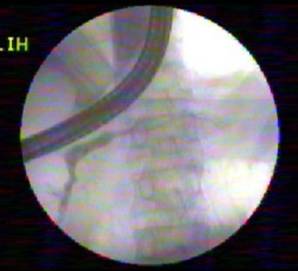

A 59-year-old male presented with painless progressive distension of abdomen of three months duration. He had been consuming 30 g of alcohol daily for the last 20 years. Clinically he was anicteric, afebrile and had tense ascites. The hematological and biochemical investigations revealed hemoglobin of 14.4 g/dL (reference range: 13.0-17.0 g/dL), white blood cell count of 10,500 cells/mm3 (reference range: 4,000-10,000 cells/mm3) (70% polymorphonuclear cells), bilirubin of 0.9 mg/dL (reference range: 0-1 mg/dL), AST of 60 IU/L (reference range: 10-42 IU/L) and ALT of 53 IU/L (reference range: 10-40 IU/L); rest of the blood parameters were normal. Abdominal computed tomography (CT) revealed enlarged caudate and left lobes of liver with relatively smaller right lobe, heterogeneous pancreatic parenchyma, collaterals and marked ascites (Figure 1). Ascites was drained and fluid analysis revealed total leukocyte count of 3,360 cells/mm3 (60% polymorphonuclear cells), protein of 1.0 g/L, albumin of 0.2 g/L, amylase of 116,963 IU/L and adenosine deaminase of 7 U/L. Ascitic fluid cultures were negative. Esophagogastroduodenoscopy showed grade II esophageal varices, small gastric fundal varix and mild portal hypertensive gastropathy. Endoscopic ultrasound (EUS) revealed evidence of chronic pancreatitis and ascites. Diagnosis of internal pancreatic fistula was made and the patient was taken up for endoscopic retrograde cholangiopancreatography (ERCP). Magnetic resonance cholangiopancreatography (MRCP) could have delineated the pancreatic ductal anatomy but not done because of a definite diagnosis of pancreatic ascites due to high fluid amylase in presence of CT scan and EUS evidence of chronic pancreatitis. Pancreatogram revealed a leak from distal part of pancreatic duct (Figure 2). Pancreatic sphincterotomy was done. A cannula was placed next to the fistula, flushed with normal saline and one mL of N-butyl-2-cyanoacrylate glue (Histoacryl®, B. Braun, Tuttlingen, Germany) was injected at the fistula site. Immediately after injection of glue, there was a bit of resistance noted on attempt to withdraw the cannula which was removed with a sharp tug. The check pancreatogram revealed sealed leak (Figure 3). A 7 Fr x 9 cm plastic pancreatic stent was placed in the pancreatic duct. The repeat ascitic fluid amylase was found to be 229 IU/L. He subsequently received low dose of diuretics as well and over the next one week ascites has resolved. His pancreatic stent was removed after 3 weeks and check pancreatogram was normal.

Figure 2. Pancreatogram showing leak (red arrow) from distal pancreatic duct. Note: guide wire (purple arrow). |